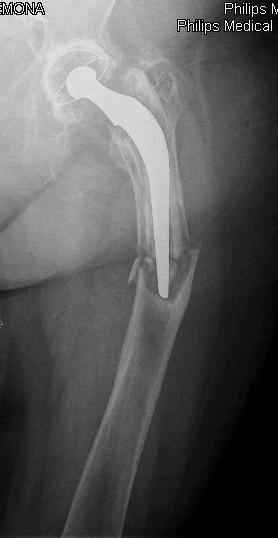

Спасибо за обсуждение. После нескольких дней тракции аппаратом сделали. Попытка закрытой репозиции не удалась из-за смещения по ширине, мешали фрагменты цемента. После их удаления репозиция получилась. Еще убрали немного цемента с ножки по латерльной стороне, чтобы обнажить 40-50 мм ее дистальной части, для плотной посадки гвоздя. Дальнейшее введение гвоздя было несложным. Протез показался нам стабильным в проксимальной части как латерально, так и медиально. Картинки в приложении.

THX for the discussion. After few days of traction by ex-fix the surgery was performed. An attempt of closed nailing was unsuccesful because of fragment translation, which was blocked by cement fragments. After removal of broken cement pieces reduction was reached "automagically". Also some cement from lateral part was removed by

chisel to expose distal 40-50 mm of the stem to allow tight fit of the nail. Further fixation by the nail was pretty easy and straightforward. Images attached. The stem looked stable in its proximal part both laterally and medially. Comments/critics are welcome.

You transformed a cemented hip prosthesis to a cementless revision hip prosthesis with a little approach.